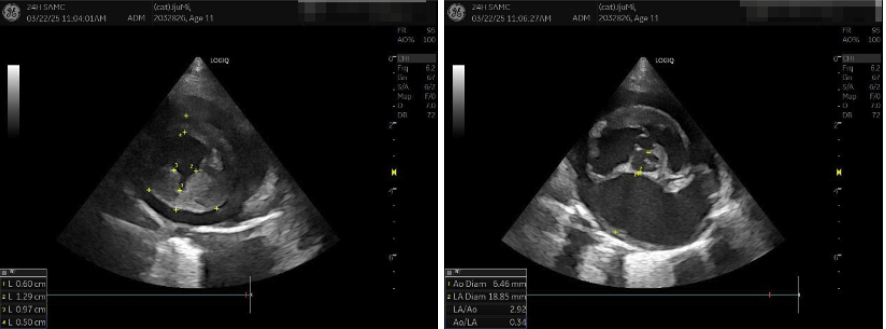

양산 고양이 제한성심근병증 내원 (좌) & 치료 후 (우) / 출처: 에스동물메디컬센터 양산점

1주일 뒤 재진에서 촬영한 X-ray에서는 심장 크기가 감소한 것을 확인하였습니다. 환자의 발열, 호흡 이상, 활력 저하 등의 증상 또한 모두 개선되었으며, 약물치료와 정기 모니터링을 통해 환자의 삶을 질을 개선하고 합병증 발생을 최대한 방지하도록 하였습니다.